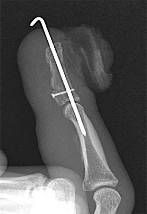

A 9-year-old boy has a history of multiple fractures. He presents with left leg pain following a minor fall. His anteroposterior

() and lateral () plain radiographs are shown. The most likely genetiCdefect would be:

Explanation

In osteogenesis imperfecta, the genetiCdefect involves type I collagen. Type I collagen is made up of two alpha-1 chains and one alpha-2 chain in a triple helix. Glycine is the smallest amino acid and is crucial for coiling of the triple helix. Mutations in the

glycine chain lead to severe forms of osteogenesis imperfecta. One should also remember the Silence classification:

Type Inheritance Sclera Severity

I AD Blue Mild form, normal teeth

II AR Blue Lethal form, die early

III AR Normal Severe, progressively deforming

IV AD Normal Moderately severe

Biphosphonate therapy can be used to slow bone remodeling and increase bone mass. With regard to the incorrect choices:

FGF receptor 3 is associated with achondroplasia. Fibrillin is associated with Marfan's syndrome.

Type II collagen is associated with spondyloepiphyseal dsyplasia.

Cartilage oligomeriCmatrix protein is associated with pseudoachondroplasia. Correct Answer: Type I collagen